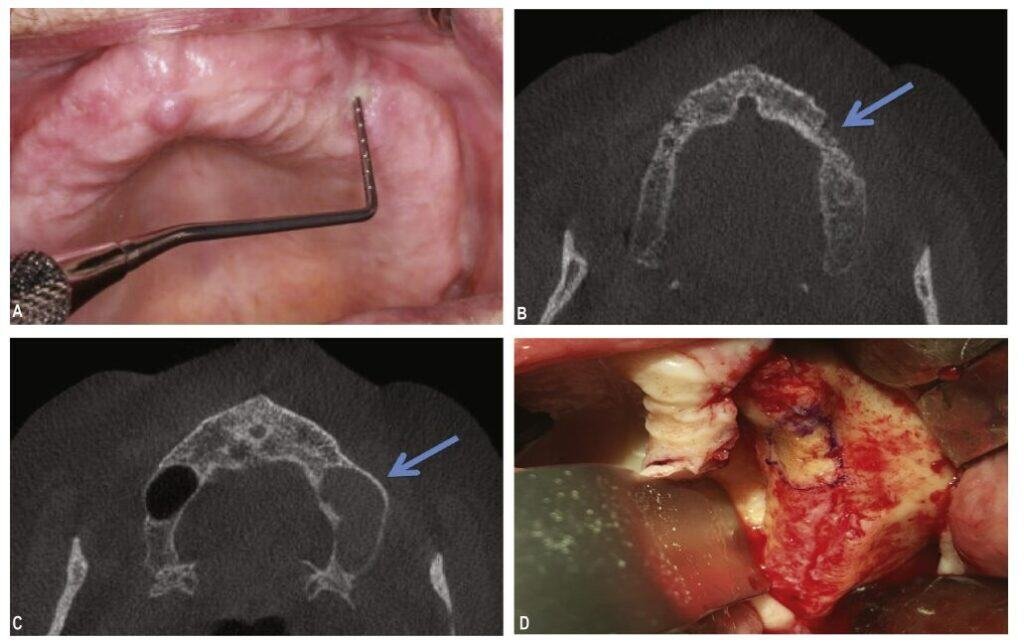

3. Why is my dentist asking for a 3D Scan (CBCT)?

Standard 2D X-rays often miss early signs. The 2024 Italian National Consensus (SIPMO-SICMF) and the 2025 Korean Consensus strongly advocate for advanced imaging.

- The Benefit: A CBCT (3D Dental Scan) allows surgeons to see inside the bone. The Italian guidelines emphasize that internal bone changes on a CT scan can confirm a diagnosis even if the bone isn’t visible through the gums yet (referred to as Stage 0).